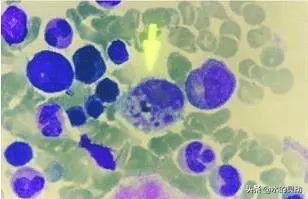

汉坦病毒又叫出血热,它的感染是由啮齿类动物传播给人的一种病毒性疾病。该病毒可引起肺部(咳嗽和气短)或肾(皮疹,腹痛,有时肾功能衰竭)的严重感染。首发症状为突起发热、头痛、肌肉疼痛,有时伴有腹部症状,随之可出现咳嗽、气促、皮疹及肾脏受累。汉坦病毒会导致人们出现汉坦病毒肺综合征,它的潜伏期是9~33天,平均14~17天。发病最初的症状与流感非常相似,体温可达38~40℃;也可伴有恶心、呕吐、腹泻、腹痛等胃肠症状;少数人表现出眼结膜充血、皮肤黏膜出血点或出血斑。